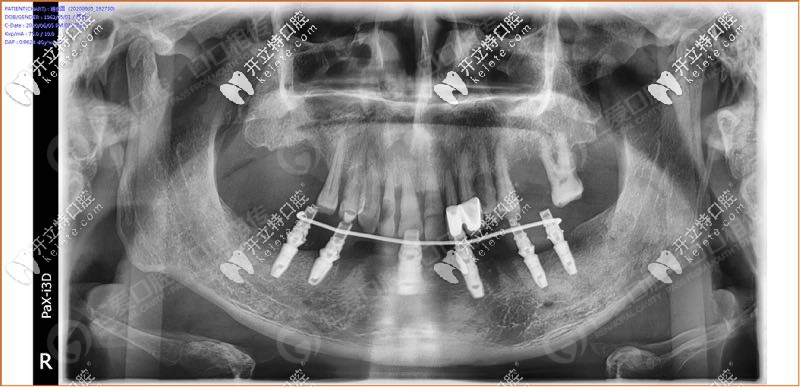

經(jīng)過我院種植醫(yī)生面診,拍片檢查發(fā)現(xiàn),31、32 、33、 34顆牙松動(3度),43顆牙也松動了, 44、45多年前做了烤瓷牙修復(fù),其余牙缺失。

具體設(shè)計方案:拔除下半口松動牙后,在33、34、36、43、44、46牙窩采用種植導(dǎo)板植入性價比高的登騰種植體,當天帶上牙冠,實現(xiàn)“當天種牙,當天用”。

手術(shù)時,我院采用的種植導(dǎo)板技術(shù),術(shù)前設(shè)計,種植體植入方向、位置、角度、深度等一目了然,導(dǎo)板輔助將種植植入到理想位置,有效避開神經(jīng)、血管等危險區(qū)域,同時也大大縮短手術(shù)時間,在拔牙窩即拔即種,沒有切口或切小口,愈合快。

順利植入6顆種植體后,把過渡性臨時假牙固定到下頜的種植體上實現(xiàn)了當天種牙,當天用的即刻負重種植牙。